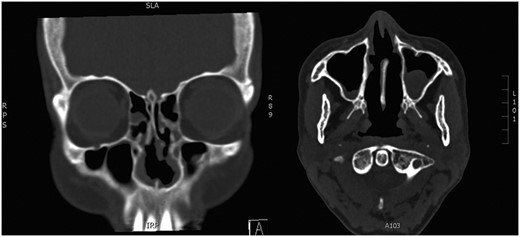

At 3 months, she had a patent nasal airway, with resolution of nasal obstructive symptoms. Follow-up CT (Fig. 4) confirmed nasal patency and also showed non-aggressive expansion of the right middle turbinate and perpendicular plate of ethmoid, again in keeping with osteoma.

Postoperative CT. Paranasal sinuses showing patent nasal airway following bilateral inferior turbinectomies.